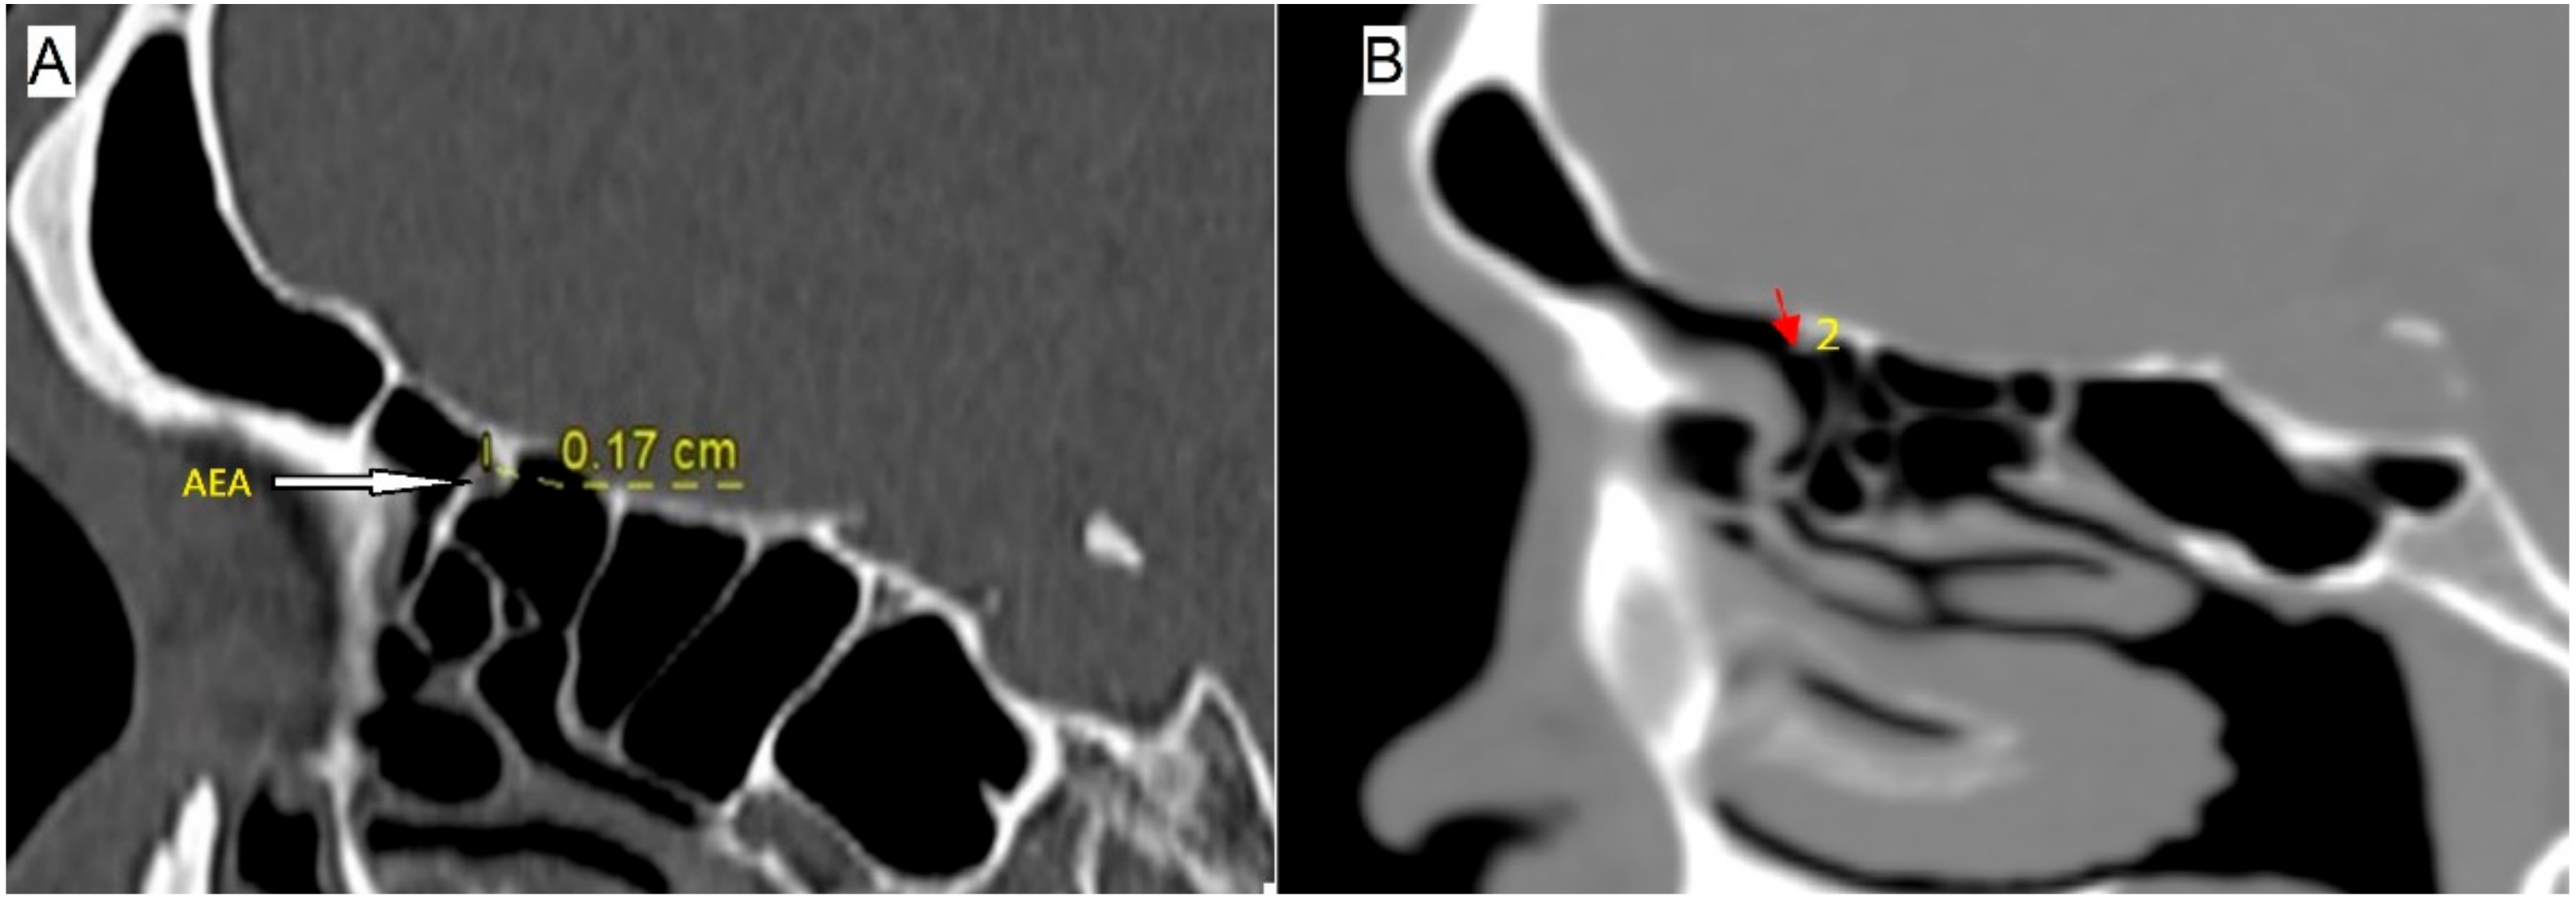

2.2. Evaluation of Anterior Ethmoidal and Middle Ethmoidal Arteries

2.3. Measurement of Anterior Ethmoidal and Middle Ethmoidal Arteries to Related Anatomical Structures